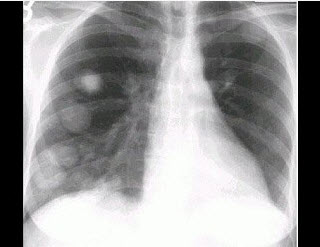

女,48岁,胸痛1周,结合图像,最可能的诊断是()

A . 肺转移瘤

B . 韦格肉芽肿

C . 肺类风湿病

D . 多发性肺脓肿

E . 肺癌

[单选题]女,48岁,胸痛1周,结合图像,最可能的诊断是()A .肺转移瘤B .韦格肉芽肿C .肺类风湿病D .多发性肺脓肿E .肺癌